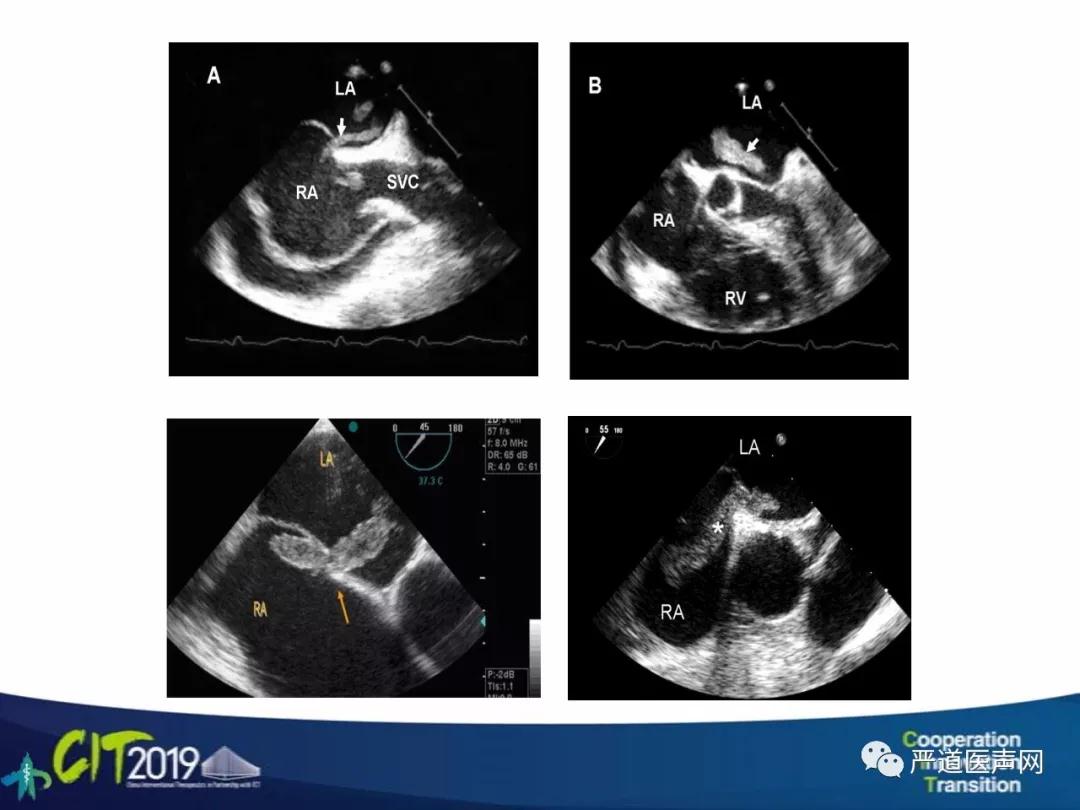

本期精品课程:PFO手术流程及临床研究更新

讲者:张玉顺(西安交通大学第一附属医院)